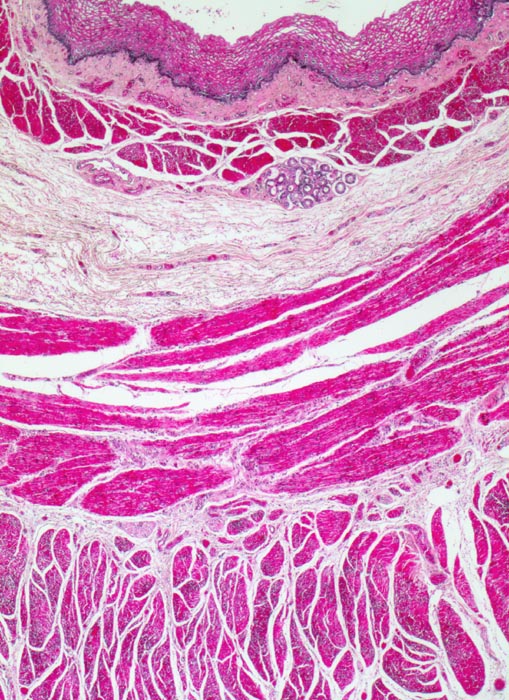

Plattenepithelkarzinome sind im gesamten Ösophagus mit Bevorzugung des mittleren und unteren Drittels (jeweils 40%) zu finden. Prädilektionsstellen sind die drei physiologischen Engen (Bereich des oberen Ösophagusmundes, Höhe der Trachealbifurkation und Kardiabereich). Die unterschiedliche Lymph- und Venenblutdrainage der oberen und unteren Teile des Ösophagus bedingt, daß die Metastasierung je nach Tumorlokalisation unterschiedlich erfolgt. Bei Diagnosestellung haben die meisten Tumoren bereits in die regionären Lymphknoten metastasiert. Hämatogene Metastasen in Leber und Lunge sind seltener. Innerhalb der Ösophaguswand breitet sich der Tumor oft (makroskopisch unsichtbar) in der Submukosa aus, und zwar mehr in proximaler als in distaler Richtung, manchmal über eine Strecke von mehr als 5 cm. Es sind sogar Tumorausdehnungen bis in den Pharynx und den Magen bekannt. Aus diesem Grund empfiehlt sich während der Operation die Schnellschnittuntersuchung der Resektionsränder .

Mikroskopisch zeigen die meisten Plattenepithelkarzinome einen mittleren Differenzierungsgrad und eine wechselnd starke Verhornung. Das fortgeschrittene Karzinom infiltriert angrenzende Strukturen wie den Tracheobronchialbaum, die Aorta und den Nervus recurrens.

• Polypoides exophytisches Karzinom.

• Tumordurchbruch durch die Lamina muscularis mucosae in die Submukosa.